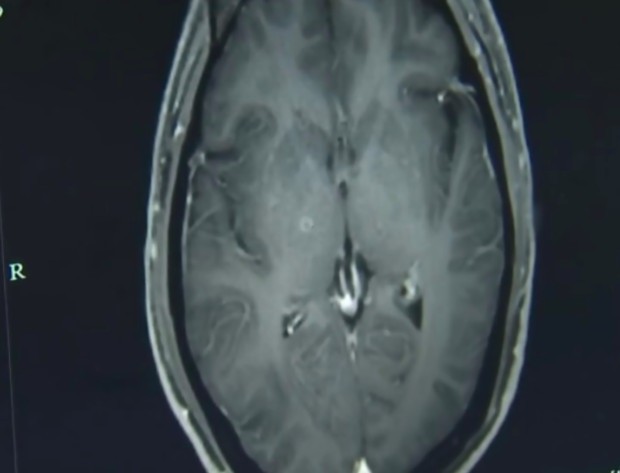

Se você é fã de carne de porco, o caso do chinês Zhu Zhongfa talvez torne você ainda mais exigente quando o assunto é o bom preparo desse alimento. Isso porque mais de 700 ovos de tênia foram encontrados no cérebro do homem, após ele ingerir um caldo com carne mal cozida.

Vale lembrar que a infecção também pode ocorrer em outras partes do corpo. Isso porque, após ingeridos, os ovos do verme eclodem por conta do fluido digestivo intestinal e permitem que a larva perfure as paredes do intestino, entrando na corrente sanguínea e chegando a diferentes partes do corpo.

Como o cérebro humano é muito vascularizado, os animais costumam se instalar por lá. Ainda assim, outras regiões também estão em risco: o próprio Zhu apresentou infestação nos pulmões.